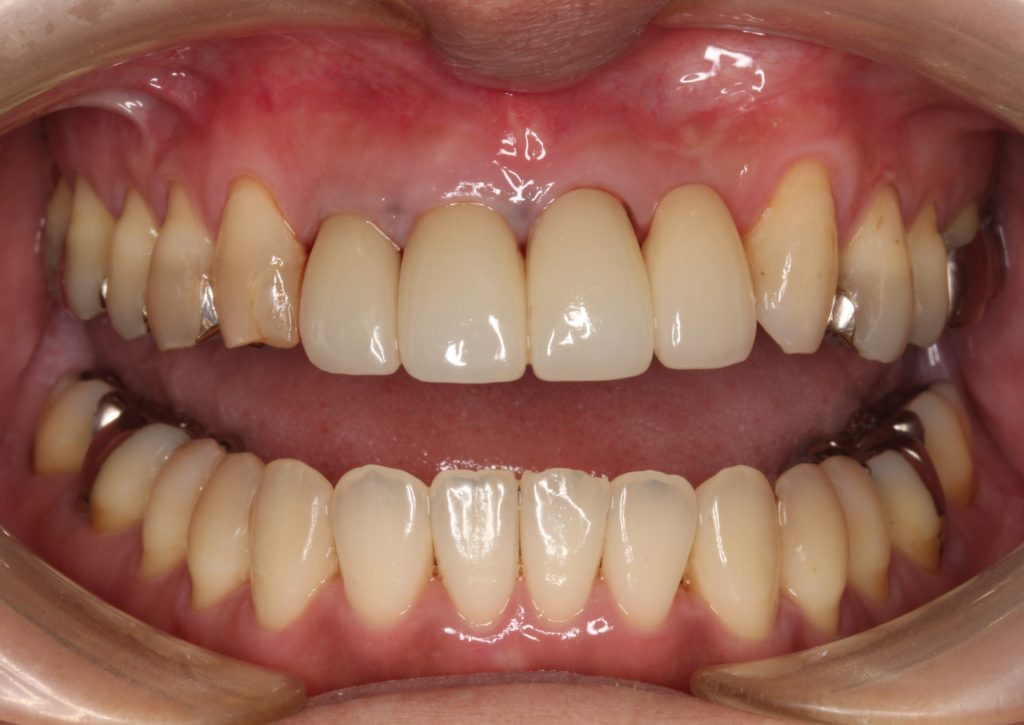

後日出来上がった歯を装着します。

下の歯の色に合わせて、白めに仕上げています。

綺麗な歯になりましたね!

最初の状態を見てみましょう。

全体的な色も綺麗に明るくなりましたし、根元の黒さも目立たなくなりました。

今回は歯のもろさを考慮して、歯を連結して仕上げています。